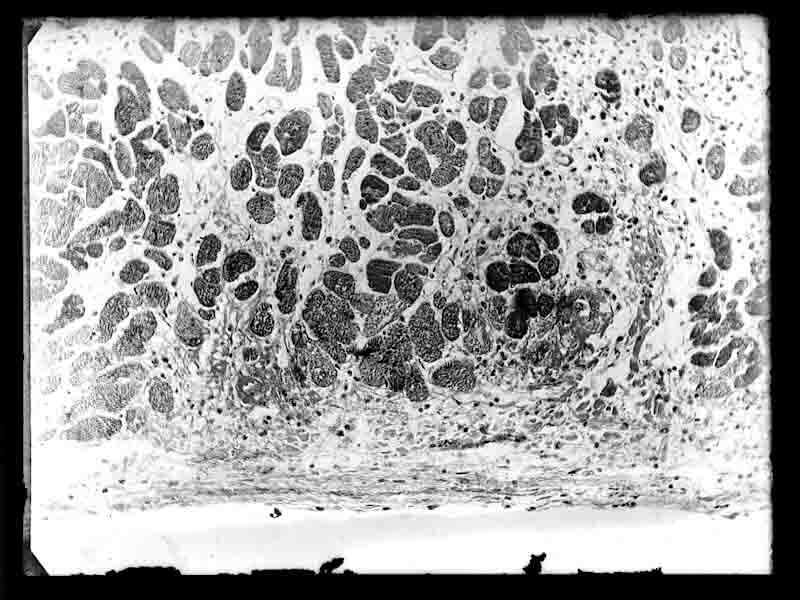

Fotomicrografia

Documentos iconográficos: 1 item (negativo de vidro p&b 9x12 cm)

Solicitação não identificada

Notação anterior: IOC-V-III-3573